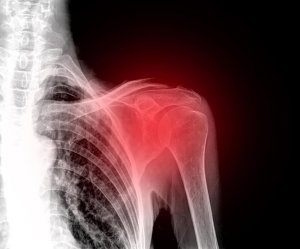

Olkapääkipu on hyvin epämukava ja invalidisoiva vaiva, sillä olkanivelen avulla liikutamme käsiämme ja olemme näin tehokkaassa vuorovaikutuksessa ympäristön kanssa. Lievitä olkapääkipua tehokkaasti näillä luonnollisilla hoitokeinoilla!

Ensiksi sinun on hyvä tietää, että olkapääkipu on yleisempää kuin ehkä luulet. Kipua, turvotusta ja liikuntakyvyttömyyttä voivat aiheuttaa erityyppiset olkapään vammat. Myös kroonista turvotusta voi esiintyä, jos vammaa ei hoideta lääkärissä.